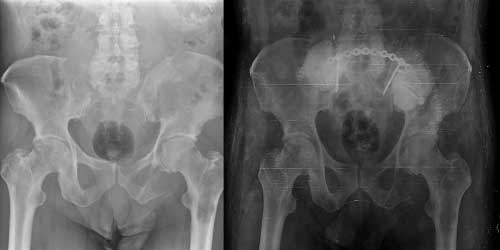

Omurga metastazı, kanserin ilk olarak iç organlarda gelişip daha sonra omurga kemiklerine yayılması sonucu oluşan bir durumdur. Çoğunlukla kan yoluyla sıçrayan bu tür metastaz, hastalarda sırt ve bel ağrısı gibi şikayetlerle kendini gösterir. Erken teşhis ve uygun tedavi yöntemleri, hastaların yaşam kalitesini artırmada kritik bir rol oynar.

Tedavide başarıyı artıran en önemli etkenlerden biri ameliyat öncesi iyi bir hazırlık ve cerrahi planlama yapmaktır. Her şeyden önce tanı doğru konmalı. Bunun için hasta iyi dinlenip, detaylı muayene edildikten sonra tetkikleri dikkatli incelenmelidir.